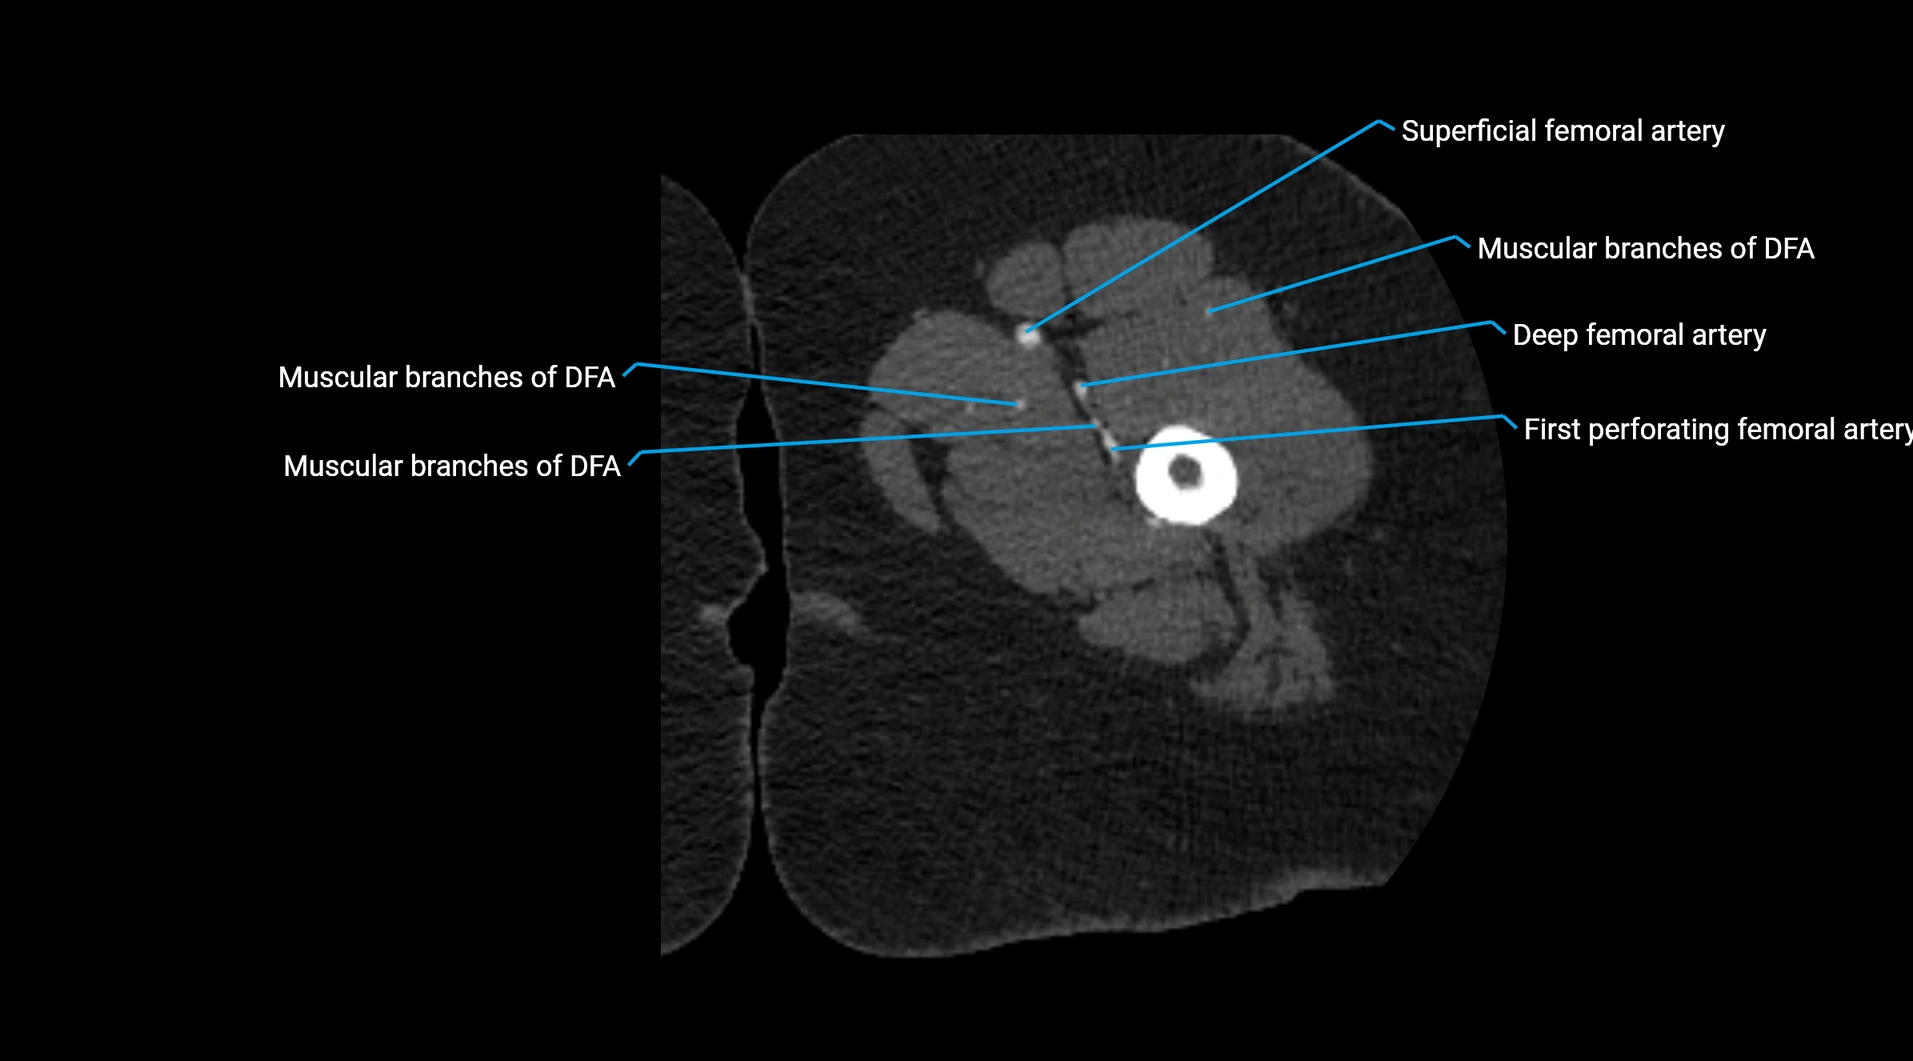

CT Appearance

Non-contrast CT:

• Appears as a tubular soft tissue structure anterior to vertebral bodies

• Calcified atherosclerotic plaques appear as hyperdense foci along the wall

• Useful for screening abdominal aortic aneurysm (AAA) size and mural calcification

Contrast-enhanced CT (CTA):

• Gold standard for abdominal aortic imaging

• Provides excellent detail of lumen, wall, aneurysm, thrombus, and branch vessels

• Multiplanar and 3D reconstructions help in aneurysm measurement, stent graft planning, and dissection evaluation

• Detects acute rupture, traumatic injury, or occlusion with high sensitivity